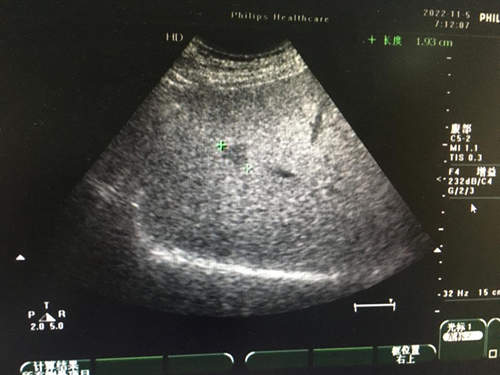

(1)轻、中度脂肪肝:肝大小正常,实质回声均匀、细密、轻度增强,轻度脂肪肝的肝内管道结构清晰,中度脂肪肝的肝内管道结构稍模糊,但仍可辨认清楚,后方回声轻度衰减,深面膈肌可显示。

(2)重度脂肪肝:肝脏体积增大,形态饱满,肝回声均匀、细密、明显增强,肝内管道结构模糊不清,后方回声明显衰减,深面的膈肌显示不清。

超声检查是公认的首选检查,是进行脂肪肝诊断、分型的最佳手段,同时需要检查肝功能。当肝功能异常,谷丙转氨酶(ALT)偏高时,可做肝脏超声弹性成像来评估肝纤维化的程度。